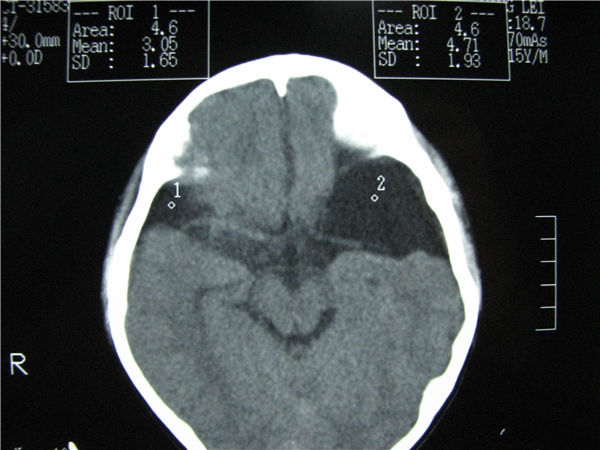

标题: CT20748:M 15Y 头痛,以前有外伤史请老师看看除了囊肿还有别 [打印本页]

标题: CT20748:M 15Y 头痛,以前有外伤史请老师看看除了囊肿还有别

m 15y 头痛,以前有外伤史请老师看看除了囊肿还有别的吗?

蛛网膜囊肿。眼拙,看不出别的,倒是看到了双侧大脑中动脉影,类似“致密动脉征”。

双侧侧裂池和纵裂池近前颅窝蛛网膜囊肿。

不能除外脑穿通畸形

无明显占位及负占位效应,考虑软化灶并脑室穿通畸形囊肿、局限性脑萎缩

蛛网膜囊肿,不能除外脑穿通畸形,支持。